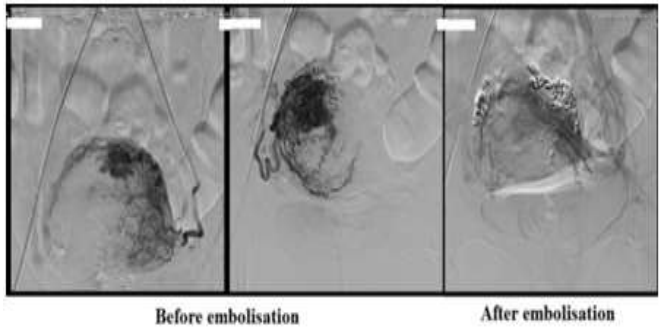

Shintre and Coelho [16] reported a 27-year-old lady who was known to have Thalassemia minor who had manifested with heavy vaginal bleeding and passage of clots over the preceding two days. She stated that she had been having continuous on and off mild to moderate vaginal bleeding pursuant to a second trimester therapeutic abortion she had undergone two months preceding her presentation. She did undergo therapeutic abortion in view of the fact that she had her chorionic venous samples which had shown that the foetus had Thalassemia major due to the fact that both herself and her husband had Thalassemia minor. The therapeutic abortion was induced with utilization of misoprostol (PGE1) tablets. The reports of the obstetrician who undertook the therapeutic abortion did document that the abortion was complete and therefore no curettage was undertaken pursuant to her abortion. She had also undergone another therapeutic abortion 8 months earlier for the same reason following chorionic villous sampling that showed Thalassemia major foetus. This therapeutic abortion was ensued by curettage of her uterine cavity for complete evacuation of her products of conception. She did not have any significant past medical or surgical history. She was noted to be pale or otherwise her general examination was normal. She had speculum examination of her vagina which showed a partially open cervical os that associated with minimal blood clots. There was no active bleeding. Her uterus was bulky, and it measured about 8 weeks to 10 weeks size as well as it was firm to soft in consistency, firm to soft with regard to consistency, mobile and associated with free fornices. The results of some of his laboratory blood tests included: Haemoglobin 9.5 grams per decilitre, platelets 3-lakhs, Serum Beta Human Chorionic Gonadotrophin (B-HCG) 35 MIU/ML which was normal, normal coagulation screen and normal liver function tests. Her blood sample was sent for grouping and saving for future use when required. She had ultrasound scan and magnetic resonance imaging (MRI) of pelvis. The MRI scan demonstrated a bulky uterus that measured 4 cm x 7 cm x 7 cm, heterogeneous lesion within the posterior wall of her uterus, lost endometrial-myometrial interface, multiple dilated tortuous blood vessels within her posterior myometrium which had suggested the likelihood of retained products of conception or gestational trophoblastic tumour which would represent placental site trophoblastic tumour, or uterine vascular malformation (see figure 1). The trans-abdominal ultrasound scan of pelvis did demonstrate an 8.8 cm x 7.5 cm x 7.5 cm bulky uterus the posterior myometrium that was very enlarged as well as heterogeneous with increased vascularity upon Doppler ultrasound scanning (see figure 2). Doppler ultrasound scanning did demonstrate a peak systolic velocity (PSV) of 121 cm / s as well as restrictive index of 0.36. The ultrasound scan also demonstrated that her endometrium was thickened within the lower uterine segment that was suggestive of retained products of conception. She had a chest x-ray which was normal. She had ultrasound scan-guided evacuation of her retained products of conception from her lower uterine segment which was sent for pathology examination. The evacuation of the products of conception did trigger active bleeding. She therefore underwent uterine artery embolization with utilization of cyanoacrylate (glue) (see figure 3). There was no evidence of active bleeding pursuant to her embolization. She was discharged on the 3rd post-procedure op day on oral antibiotics and haematinics. Pathology examination of the tissue did show degenerated and necrosed bits of decidua as well as few degenerate chorionic villi that were admixed with fibrin and blood. The degenerate products of conception did not show pathology examination features of placental site tumour trophoblastic. At her 6-weeks follow-up assessment she stated that her vaginal bleeding had diminished gradually over a period of 4 weeks and the bleeding stopped completely after 4 weeks. She had ultrasound scan of her pelvis with Doppler scan which did show diminished size of the arteriovenous fistula and with diminished vascularity (see figure 4). Shintre et al. [16] stated that the first case of AVM of the uterus was reported in 1926. [17]

Figure 3: Digital subtraction angiography (DSA) showing bilateral hypertrophy of uterine arteries that feed a tortuous, hypertrophic arterial mass with capillary lakes and post uterine AVM embolization film demonstrating successful embolization of the feeding vessels of AVM with the help of N-butyl cyanoacrylate (glue). Reproduced from: [16] Shintre H S, Coelho K S. Managing Uterine Arteriovenous Malformation (AVM) Is Like Dealing With Raging Wildfire Awaiting A Spark: Better Be Extremely Cautious & Be Ready With Counter Measures Like Uterine Artery Embolization (UAE). Obstet. Gynecol. Int. J. 2017; 6(1): 00195 DOI: 10.15406/ogij:2017.06.00195

https://medcraveonline.com/OGIJ/managing-uterine-arteriovenous-malformation-avm-is-like-dealing-with-raging-wildfire-awaiting-a-spark-better-be-extremely-cautious-amp-be-ready-with-countermeasures-like-uterine-artery-embolization-uae.html under copy right ©2017 Shintre, et al. This is an open access article distributed under the terms of the, which permits unrestricted use, distribution, and build upon your work non-commercially